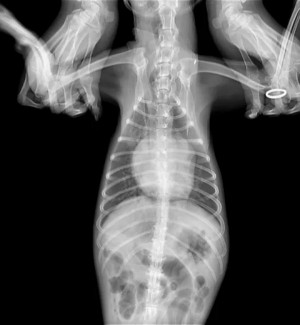

临床检查:精神状态很差,,听诊二尖瓣重度反流,心杂音重,站立不稳

BCS 5/9 体温37.5度,呼吸一分钟80次

肺水肿,二尖瓣退行性病变MMVD C期